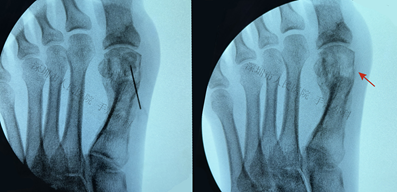

图13:术中定位内侧籽骨(左图),并切除籽骨(右图,箭头)